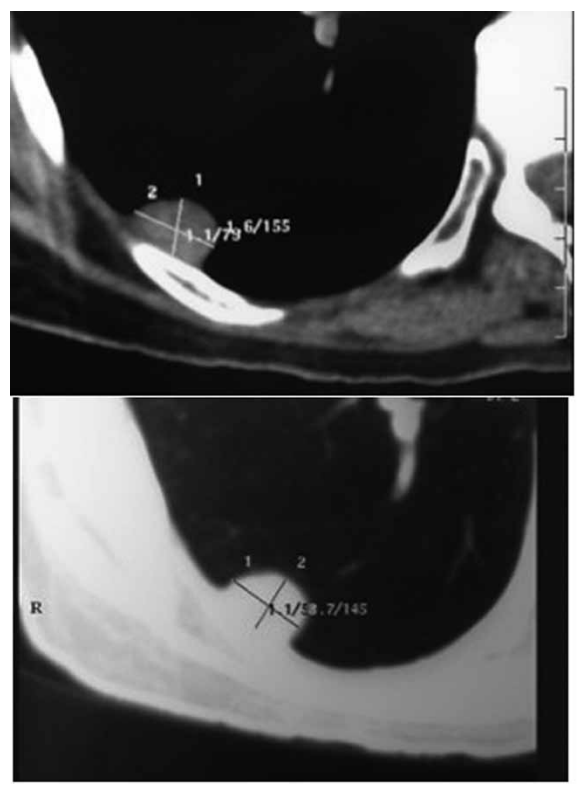

Paciente 46 anos, com tosse persistente pós-Covid-19.

Relatou um episódio de desmaio há 20 dias, atribuído à

hipoglicemia na época. Procura serviço médico, e é submetido à tomografia de tórax, conforme demonstrado a seguir:

(Arquivo pessoal; imagens usadas com autorização)